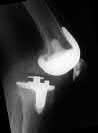

What is the most likely mechanism of failure for the patellar component shown: